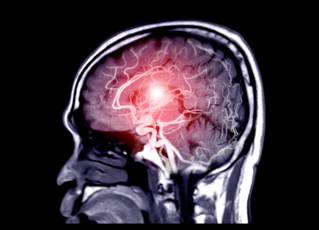

L’insuffisance circulatoire cérébrale signifie que le cerveau n’est pas suffisamment irrigué par les artères vertébrales et les carotides L’ICC est donc soit carotidienne, soit vertébrobasilaire Du fait d’une anomalie au niveau de ces artères, le cerveau ne reçoit plus la quantité d’oxygène dont il a besoin pour. L'accident vasculaire cérébral, l'AVC apparaît lorsque le cerveau n'est plus irrigué par le sang Cet arrêt brutal de l'irrigation prive les zones cérébrales d'oxygène L'AVC est la deuxième cause de mortalité dans le monde, où il touche près de quinze millions de personnes aussi bien dans les pays développés que dans les pays en. L’insuffisance circulatoire cérébrale signifie que le cerveau n’est pas suffisamment irrigué par les artères vertébrales et les carotides L’ICC est donc soit carotidienne, soit vertébrobasilaire Du fait d’une anomalie au niveau de ces artères, le cerveau ne reçoit plus la quantité d’oxygène dont il a besoin pour.

Un cerveau bien irrigué par votre sang est essentiel pour conserver de bonnes facultés mentales Or, cela n’est possible que si vos vaisseaux sanguins sont sains et solides Cela passe par un mode de vie sain, sans tabac et avec beaucoup de légumes frais et colorés, riches en antioxydants, et aussi beaucoup de petits fruits rouges et noirs. L'accident vasculaire cérébral se produit lorsque le cerveau n'est plus suffisamment irrigué par le flux sanguin Il peut s'agir d'un simple ralentissement ou d'un arrêt si un vaisseau sanguin se bouche par exemple Peu importe, il s'agit d'une urgence car mal irrigués, les neurones meurent, ce qui peut provoquer des lésions et. Au bout de 10min t'es tout rouge et t'as mal Dans cette position tu es soumis à 1G c'estàdire que ton sang tombe vers ton cerveau par gravité, et a plus de mal à remonter vers les jambes, le coeur n'étant pas fait pour pomper dans ce sens !.